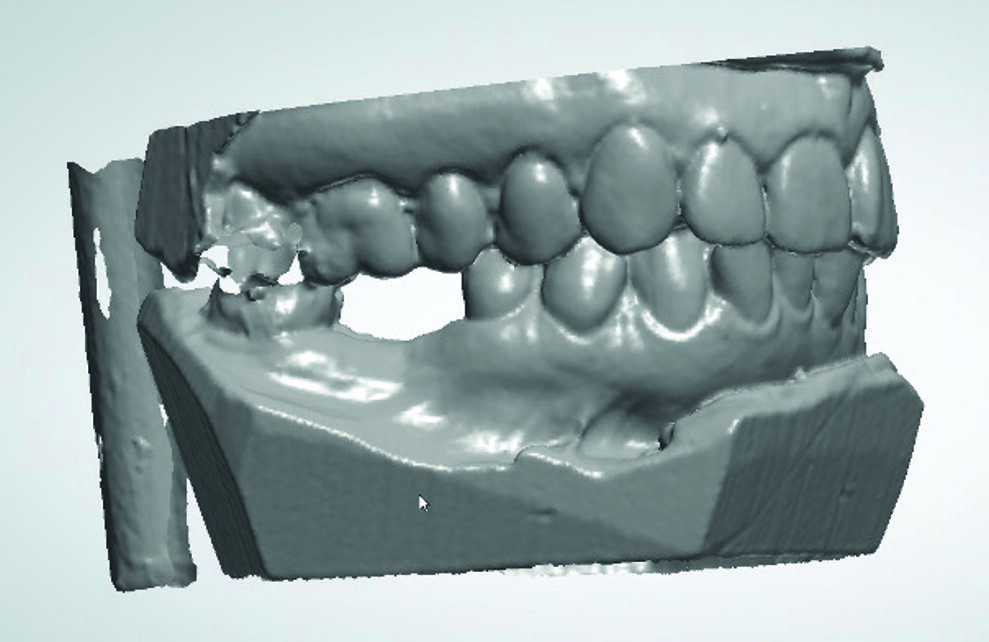

L’empreinte dentaire en silicone a été coulée puis le modèle en plâtre numérisé avec un scanner de table. Cette étape peut aussi être réalisée à l’aide d’une caméra optique (Fig. 3).

Grâce au logiciel d’implantologie Implant Studio de 3shape, nous avons pu visualiser la largeur et la hauteur de la crête édentée, afin d’étudier la faisabilité du projet prothétique.

Fig. 3 : Image du scannage des empreintes au plâtre.